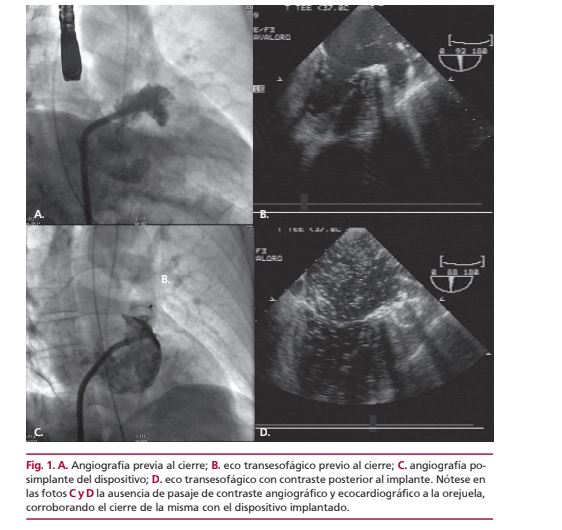

Cierre percutáneo de orejuela izquierda

IMÁGENES EN CARDIOLOGÍA